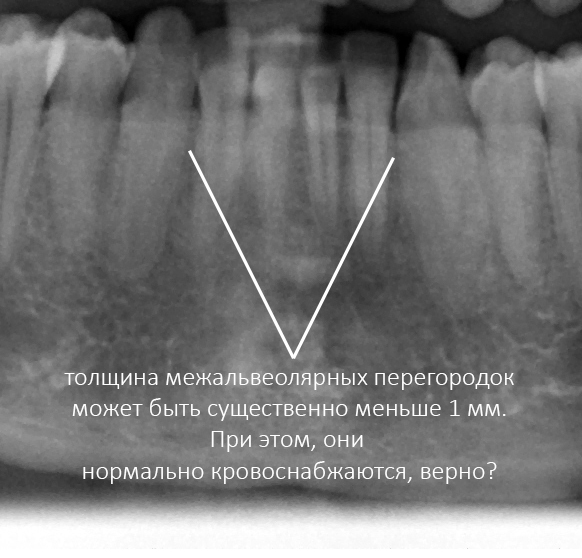

Рекомендации по установке имплантов. Для всех. Часть V.